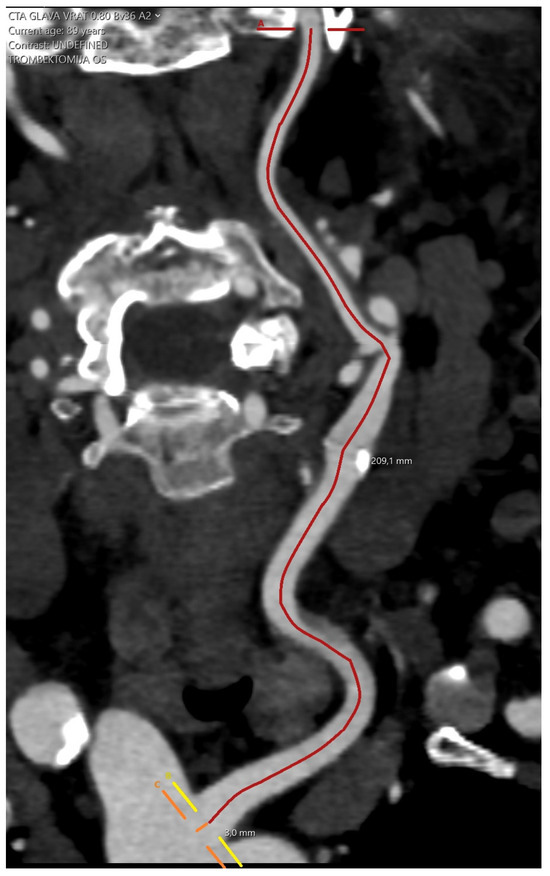

2.2. Arterial Tortuosity Measurement and Definition